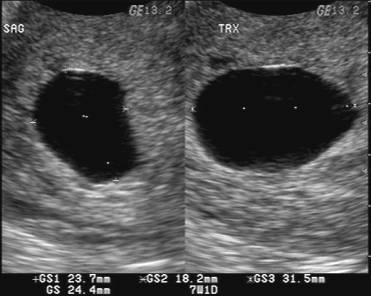

10 Tanda Tanda Hamil Kosong - Penyebab, Perawatan dan Pencegahan - Hamil .co.id

10 Tanda Tanda Hamil Kosong - Penyebab, Perawatan dan Pencegahan - Hamil .co.id